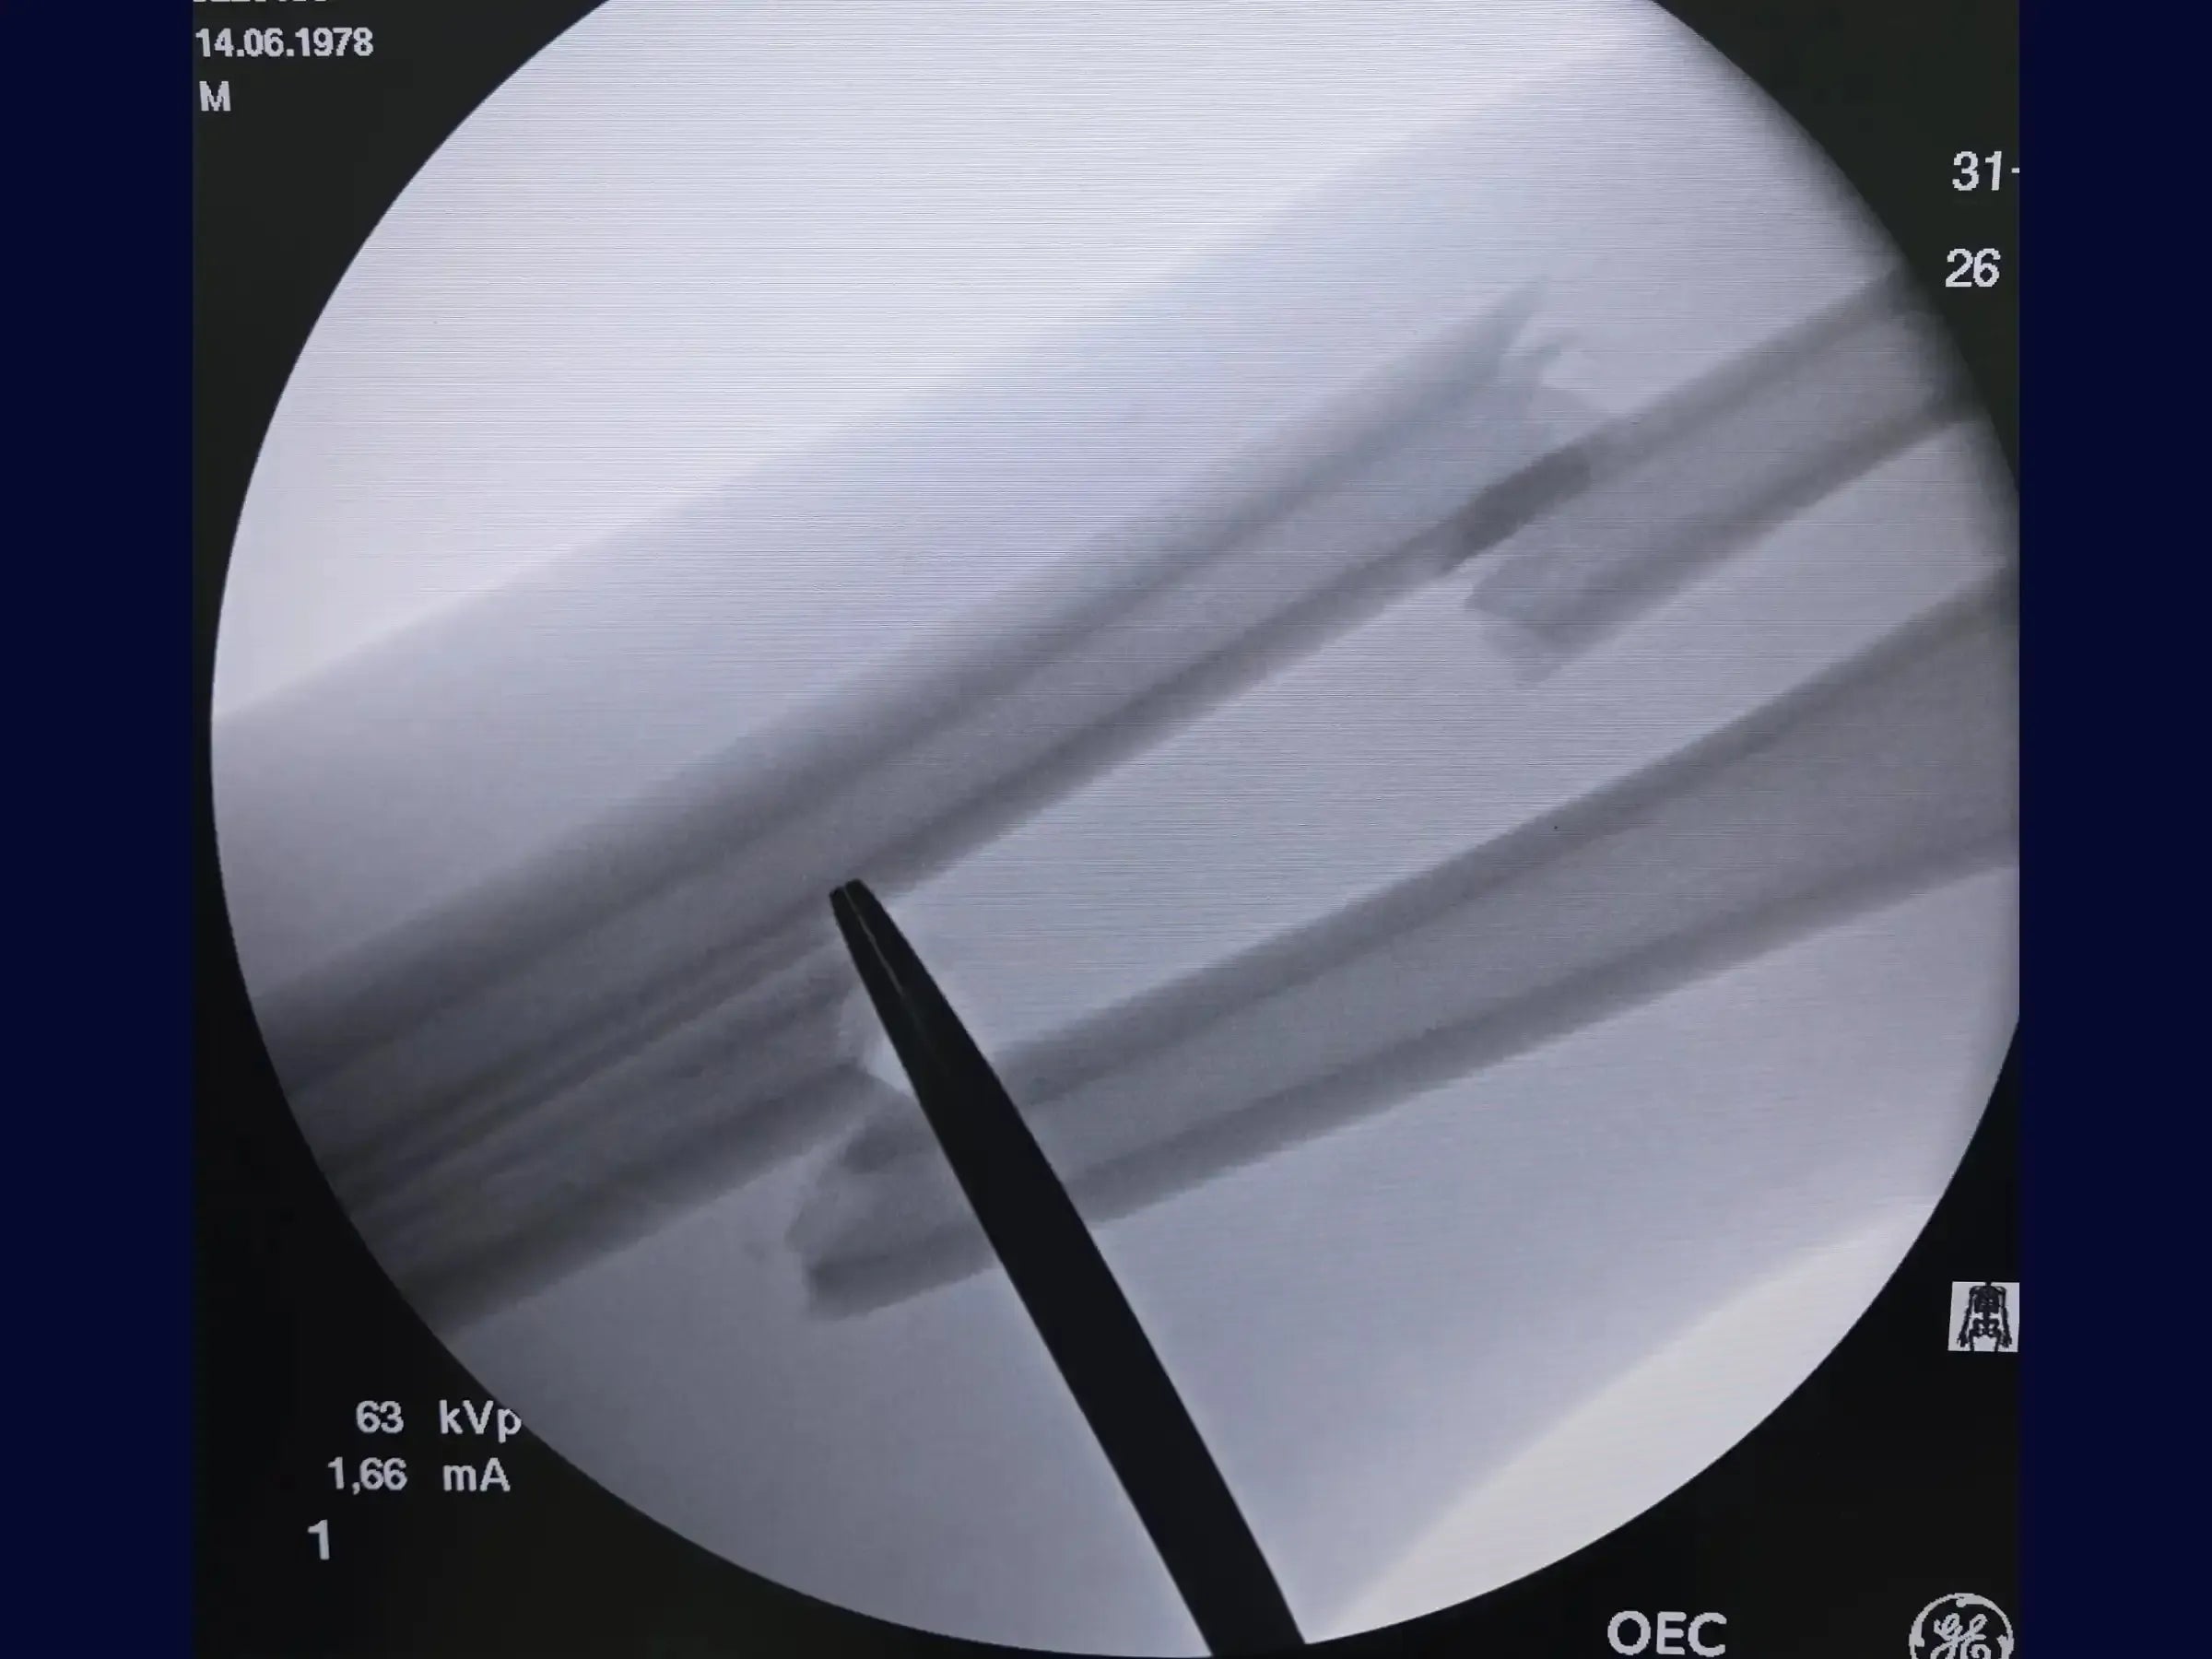

- Planejamento e Marcação: Aprenda a marcar e palpar o tubérculo de Lister e o epicôndilo lateral, traçando uma linha entre eles. Utilize a palpação muscular para definir o local exato da incisão cutânea e o intensificador de imagem para localizar o sítio da fratura.

- Identificação e Limpeza da Fratura: Palpe o fragmento proximal do rádio e defina a trajetória em direção ao osso com o dedo indicador. Faça contato suave com o bisturi na superfície óssea para buscar o ápice e o fragmento proximal, mantendo a dissecção ao longo dos planos anatômicos e expondo as extremidades da fratura. Limpe as bordas da fratura para encontrar um ponto de referência para a redução.